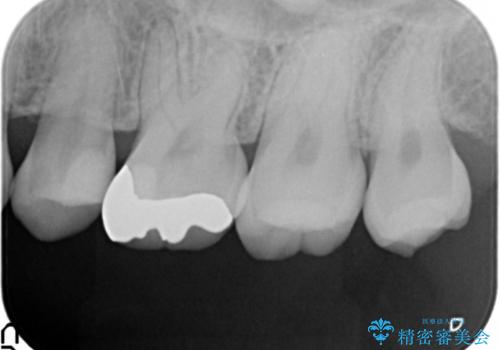

- 検診で当院を受診され、X線写真検査により大きな虫歯が見つかった症例です。

歯の種類、かかると予想される咬合力負担、残存歯質、審美性等々を考慮し審美的なセラミックインレー、力に強いゴールドインレーをそれぞれ選択し修復を行いました。